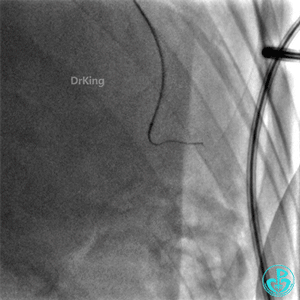

右冠脉支架通畅无狭窄,右冠脉给前降支远端提供逆向侧支循环。

EBU指引导管左冠脉造影显示粗大前降支中段闭塞,闭塞段近端有对角支发出,前降支同侧逆向显影,闭塞段不长。